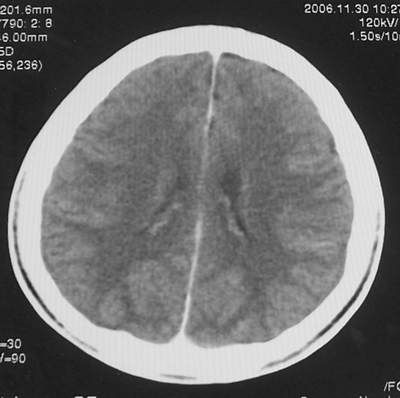

患者、男、18y,头痛5天入院。

左小脑、右丘脑区低密度影,无明显强化及占位表现,男18y,先考虑脑部炎性病变,如脑炎、血行播散性感染等,建议结合临床如脑脊液检验。

单独看左侧小脑半球的不规则形囊性低密度灶,从发病部位、年龄以及无强化、无占位效应的特点可以考虑毛细胞瘤型星形细胞瘤。同样,如果单独看右侧丘脑的近圆形低密度,也可以考虑囊变形星形细胞瘤。只是胶质细胞瘤一般为单发直接浸润、蔓延生长,而不是在脑内同时出现多个病灶,且瘤周没有一点儿水肿,暂时不予以考虑。

脑炎倒是首先可以考虑,只是临床症状、病史不很符合,建议狼兄仔细了解病史以及其他临床资料。

同时,现在已经进入冬天,一氧化碳中毒也需要考虑进去。不知道增强是什么时间做的,与平扫间隔几天?如果中间时间比较久而且进行吸氧等治疗,则平扫所示右侧颞叶密度比较低、右侧小脑半球以及脑桥也似有片囊状低密度,但在增强却没有发现就可以比较合理的解释了。